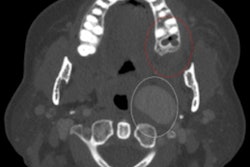

Most likely, these cases were misdiagnosed based on their radiographic and clinical presentations, as well as the treating clinician's judgment. The misdiagnosed lesions were often located in the maxillary and mandibular anterior and premolar regions, they wrote.

Due to the significant number of potentially misdiagnosed lesions, clinicians should conduct a thorough review of differential diagnoses when a patient presents with a cystic lesion in the interbicuspid area, Deeb and colleagues wrote.